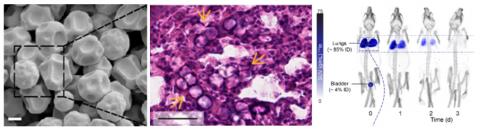

Drug delivery to the lungs and tumors with embolizing microspheres

Intravenously injected microspheres of 12 μm will reach the lungs and then get stuck in the capillaries, where they can release drugs (e.g., antimicrobial drugs, anticancer drugs) while slowly degrading. This project is about making drug releasing microspheres of the appropriate size, measuring the release kinetics, and quantifying the drug that reach the target area and induce a treatment response.